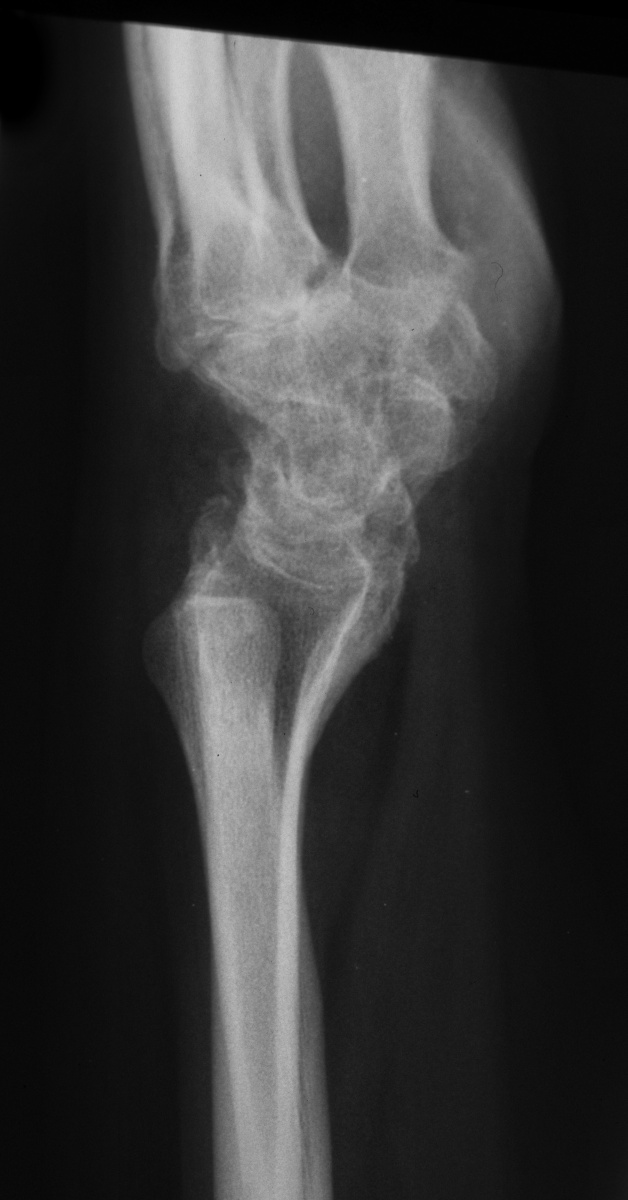

| She had progressive deterioration over two years with worsening pain and instability. |

| Initial Films: |